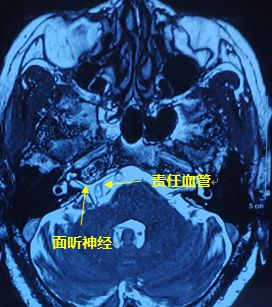

辅助检查MRI提示:“右侧面听神经走行区见关系密切血管,考虑责任血管;头颅MRA未见明显异常;双侧侧脑室周围脑白质脱髓鞘表现。"婆婆确诊为面肌痉挛,可以通过手术治疗!

术中可见粗大的椎动脉及其分支自面神经腹侧压迫,考虑此为责任动脉。将血管与面神经及其进出脑干区域分开,置入Teflon棉,彻底减压。电生理监测侧方扩散波消失。